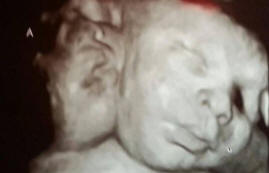

Tällaisia lapsia – yksi miljoonasta, lapsella on kaksi yksinään toimivat päät, mutta yksi ruumis ja yksi sydän sekä vanhemmat erittäin onnellinen täydentää perhettä.

Asa ja Ali Hamley syntyivät Robinin 38 vanhemmalle ja Michelle. Lääketieteen kielellä niiden poikkeamaa kutsutaan kaksisuuntaiseksi parapagus, toisin sanoen kaksosten tila, kun kaikki elimet ovat ulkopuolella lukuun ottamatta tavoitteita, heillä on yhteistä.

Tämä tapaus on mielenkiintoinen, koska yleensä tällaiset lapset eivät selviä. Jokaisessa tuhannesta tapauksesta nainen voi tulla raskaaksi tällaisen lapsen kanssa, mutta vain yksi kaksipäinen lapsi miljoonaa tavallista lasta kohti onnistuu selviytymään.

Asalla ja Elillä on kolme keuhkoa, lukuun ottamatta kevyitä sydämen häiriöt, heidän ruumiinsa on kunnossa.

Koska lähes kaikki elimet ja verenkiertoelimistö kaksoset yksin kahdelle, niitä ei voi jakaa, mikä säästää henkeä molemmille.